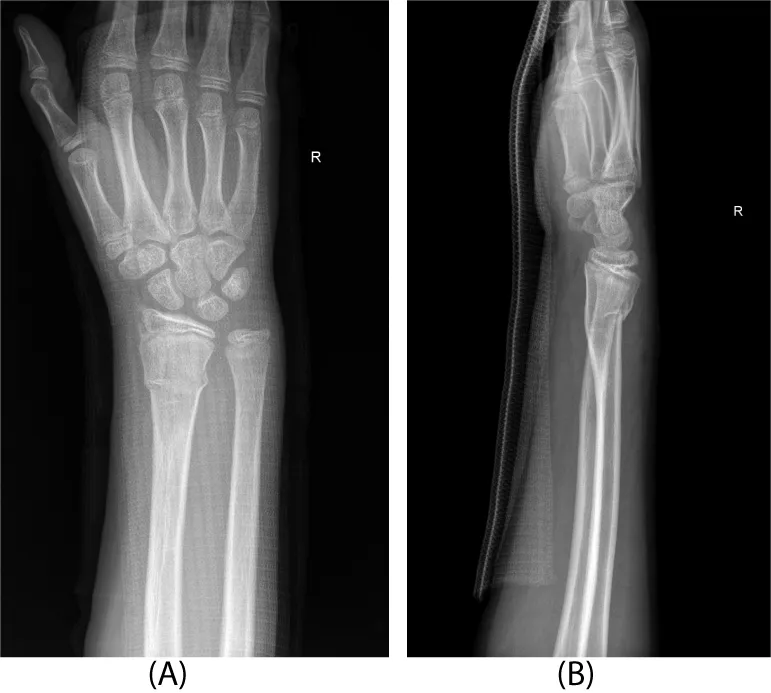

Three days after injury, consent was obtained, and the patient was taken to the operating room. There he underwent a manipulative closed reduction. Once reduction was obtained, percutaneous pin fixation was utilized to stabilize the fracture. Under flouroscopic guidance, two smooth 0.062 inch Kirschner wires were placed into the radial styloid tip and across the fracture site (Figure 2). Both pins were placed uneventfully with one attempted insertion. There were not multiple passes. The patient was then placed in a short arm cast that was split in the operating room.

The patient remained immobilized in a short arm cast until 5 weeks post-operatively. At that time, he was taken back to the operating room for Kirschner wire removal. A post-operative splint was placed for one additional week. At that time, radiographs revealed complete healing of the fracture in adequate position and therapy was initiated. At twelve weeks post-operatively, the patient was noted to have full wrist mobility and he was allowed to progress with activity as tolerated. Radiographs revealed complete healing of the fracture and the physis appeared un-affected (Figure 3).